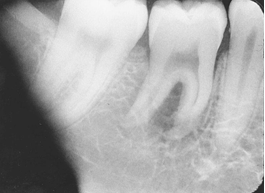

What is the problem with this Foreshorteningl X-ray?

Excessive vertical angulation, Short teeth with blunted roots

How would you resolve this Foreshortening X-ray?

Move PID